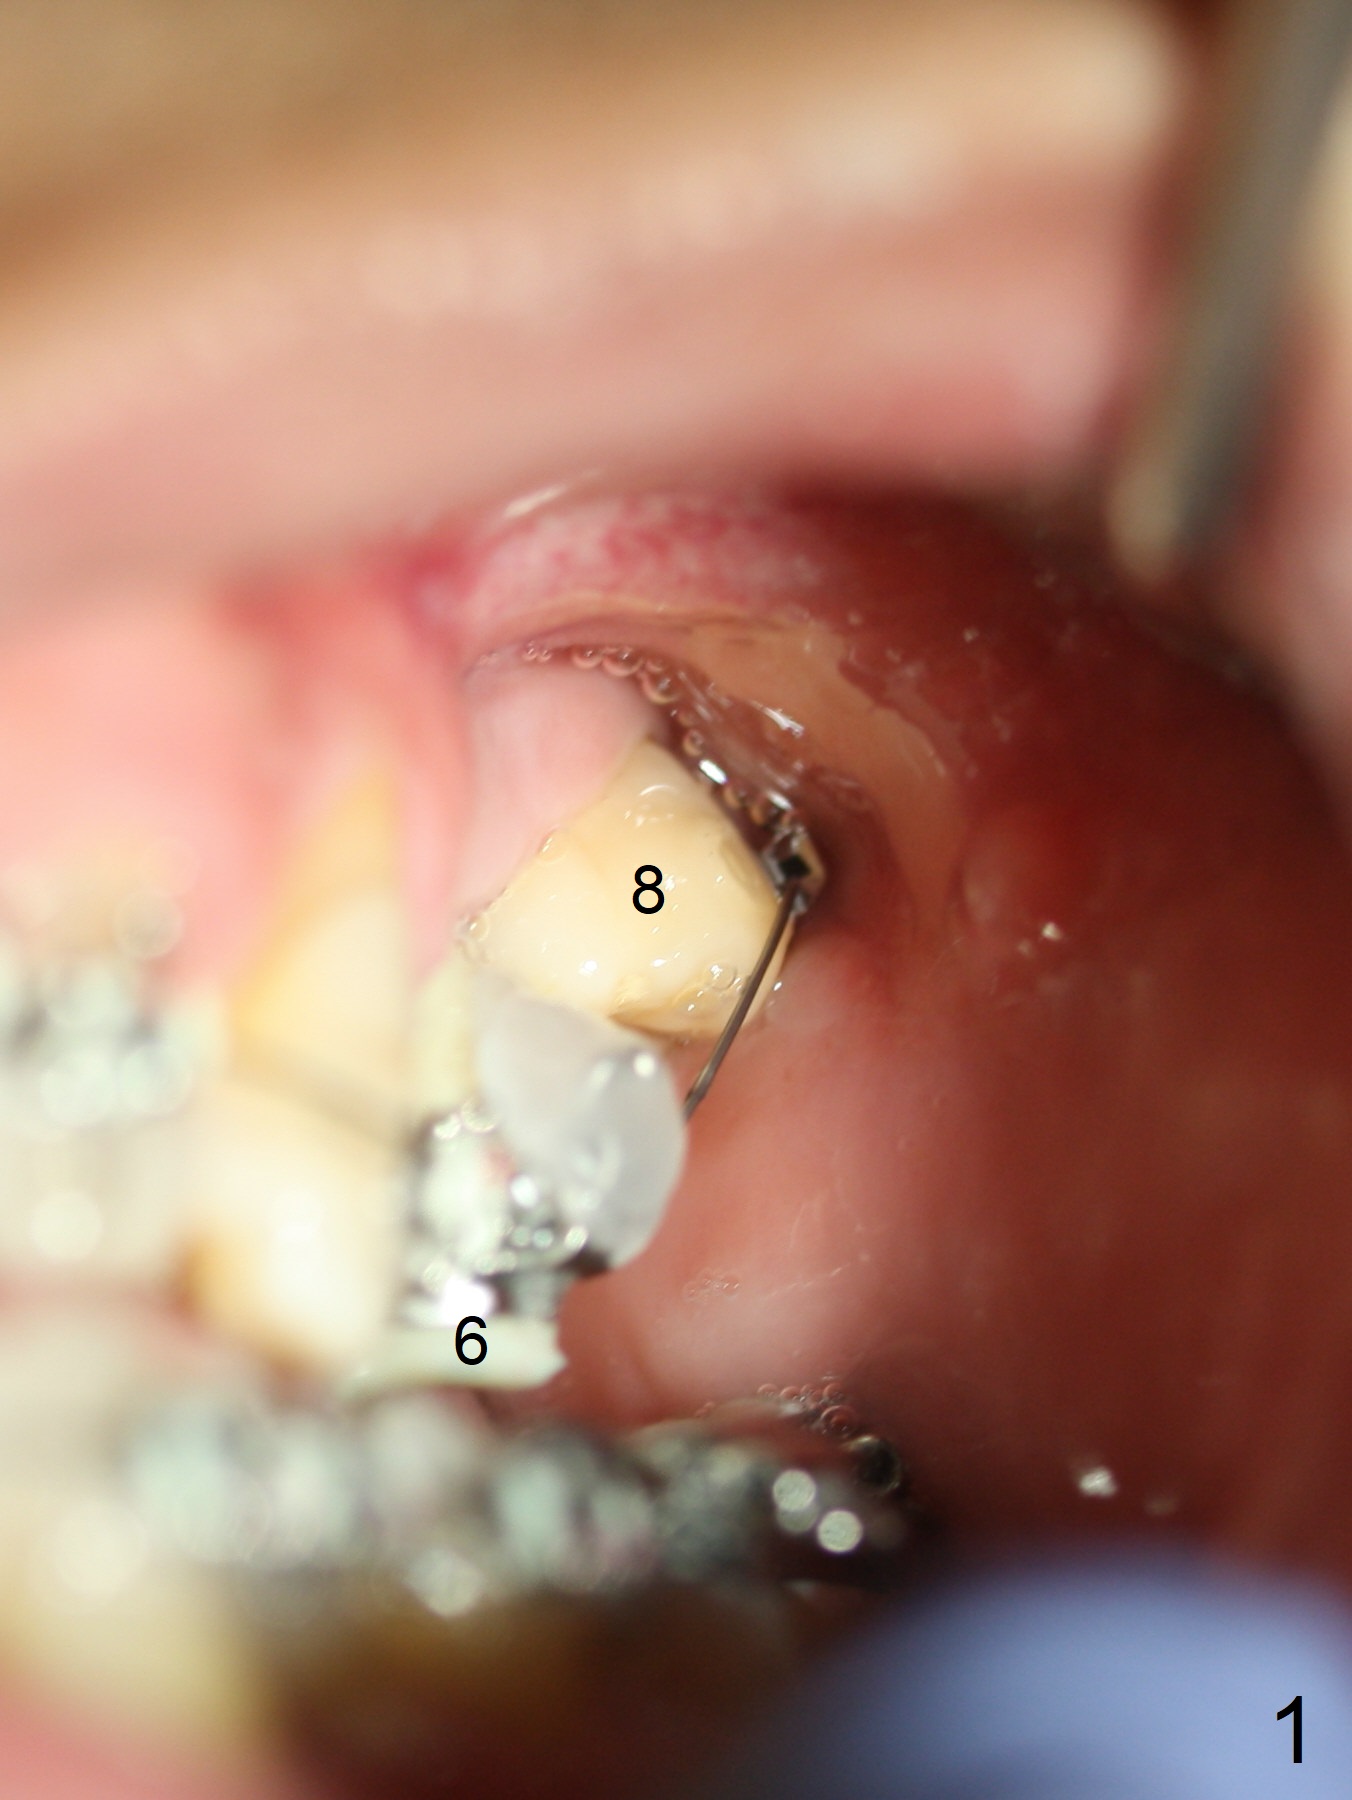

Extrusion of UL8

The provisional at UL6 (implant, as an anchor) is refabricated with normal overjet with LL6 prior to bracketing and banding for comprehensive orthodontics. There is discrepancy of bracketing/banding between UL 6 and 8 (Fig.1,2 (12, 14 niti wires (upper and lower arches)). The upper wire is also roller-coaster between UL3 and 6 (Fig.3).